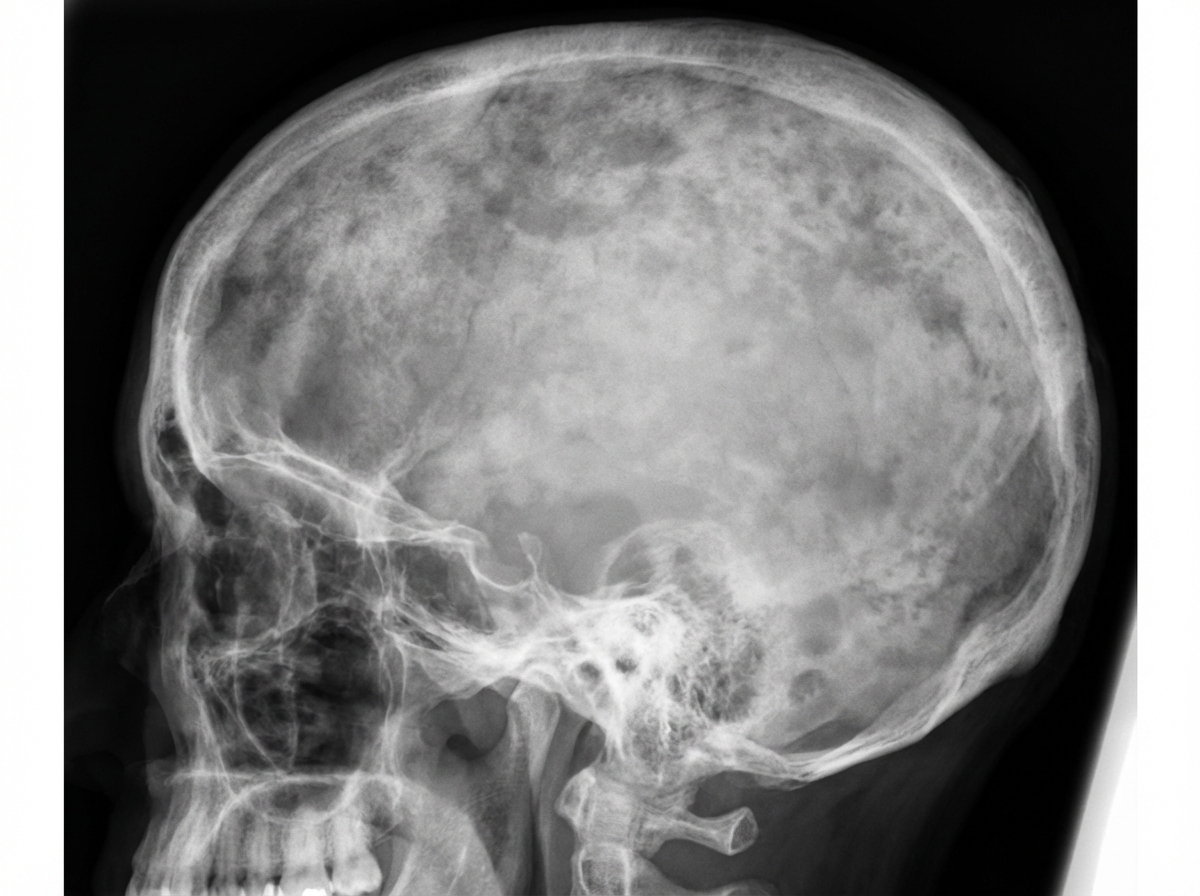

A 58-year-old man comes to the physician because of a 6-month history of headaches and back pain. Examination shows mild sensorineural hearing loss. Serum concentration of alkaline phosphatase is increased. An x-ray of the skull is shown. The most appropriate pharmacotherapy for this patient is a drug that has which of the following mechanisms of action?